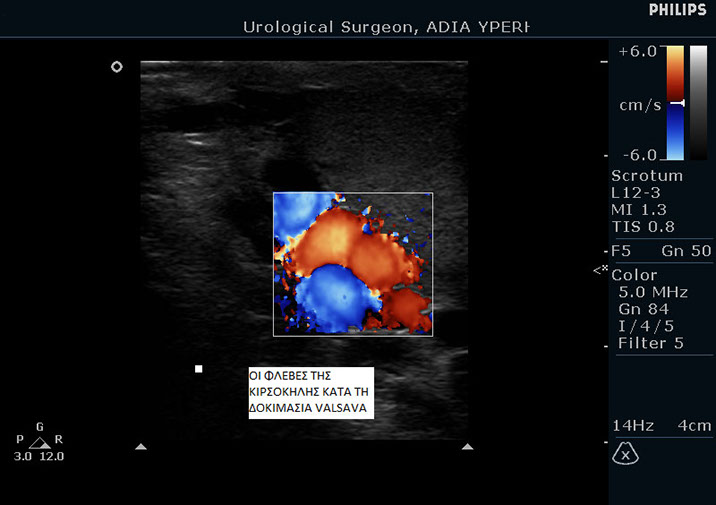

Η διάγνωση της κιρσοκήλης γίνεται πάντα από ουρολόγο με την βοήθεια έγχρωμου υπερηχογραφήματος TRIPLEX.

Ασθενής με κιρσοκήλη 3ου βαθμού.

Παρατηρήστε πως διαγράφονται οι φλέβες εντός του οσχέου. Παρακάτω μπορείτε να δείτε το triplex του ίδιου ασθενή.